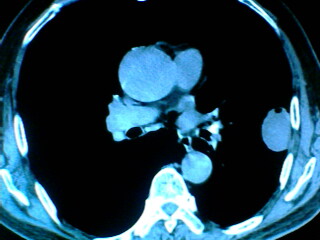

老年男性患者,右侧胸疼1月余(不是左侧),无其他症状

左肺外周类圆形病灶,其内低密度,可见液平及气影,周围肺文理见渗出样变,考虑左肺外周带肺脓肿。

左肺舌叶胸膜下卵圆形囊性肿块,内有液-气平面,邻近胸膜无增厚,没有肺窗,周围情况显示不清,考虑胸膜下肺囊肿并感染,病人年龄较大,有胸痛应警惕其他,但神经源性肿瘤暂不考虑。